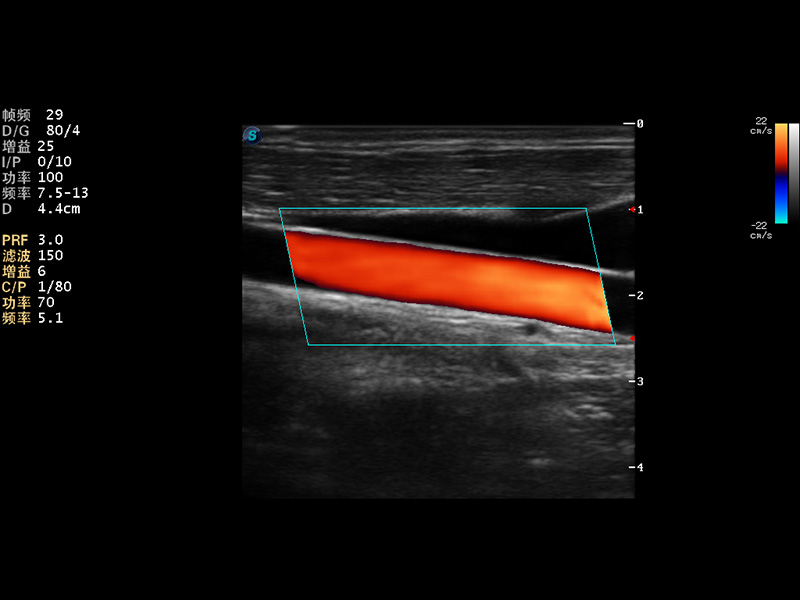

随着开立医疗超声设备核心技术的提升及临床应用领域的拓展,公司2014年全新推出全数字S12系列超声彩色多普勒诊断仪,真正意义上实现了“小身材、大智慧”的设计理念,外观小巧灵活,内在性能强大。即兼顾了全身临床应用,又拓展了多种高级成像功能,轻松满足临床应用日趋多元化的需求。

成像技术

组织多普勒成像